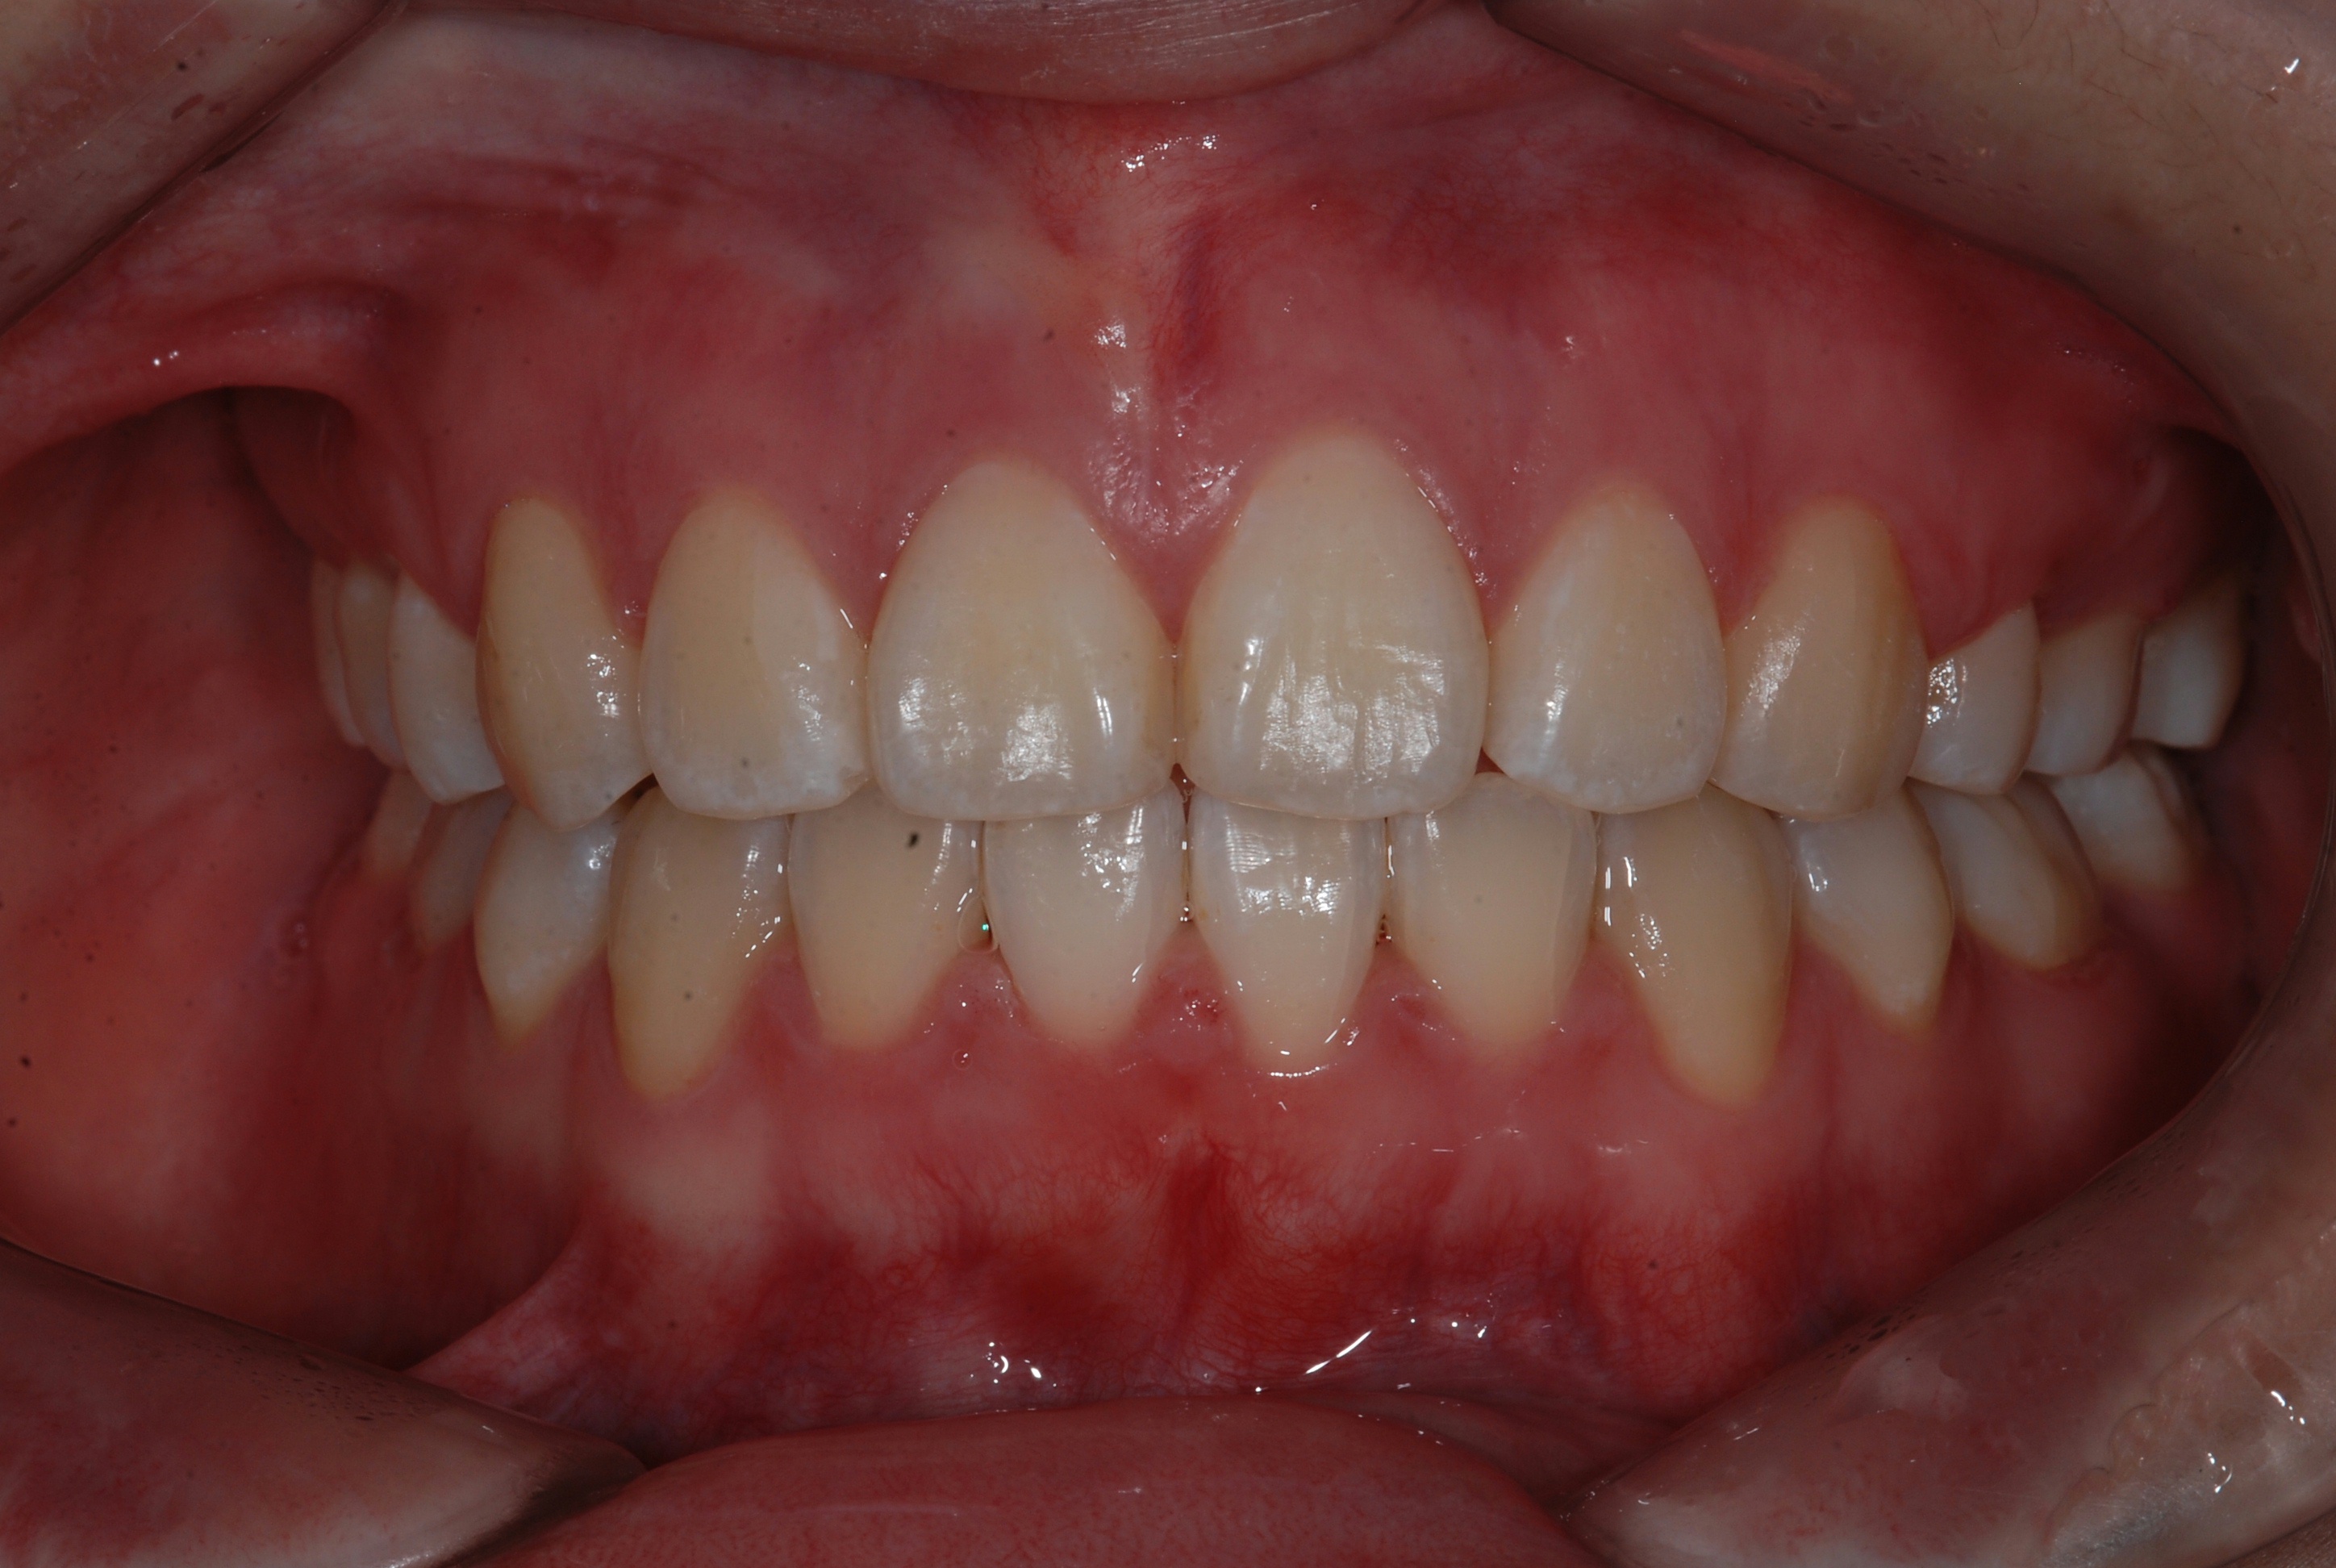

치료 후 사진입니다.